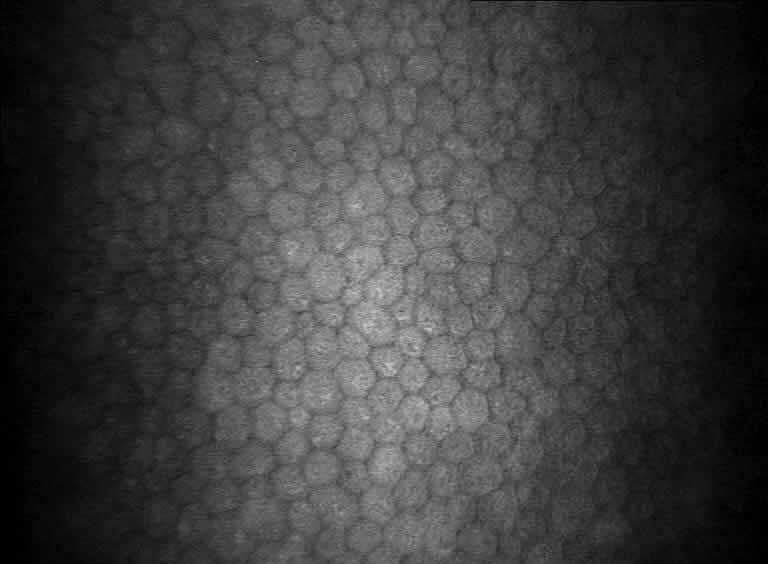

Epiretinal membranes are a disease of the retinal surface, that may affect visual acuity acuity and cause metamorphopsia, occurring in approximately 20% of the population older than 60 years The aim of this study is to compare the novel ILM sharkskin forceps with a conventional ILM forceps utilizing iOCT assistance during surgery at this “grasp site”.